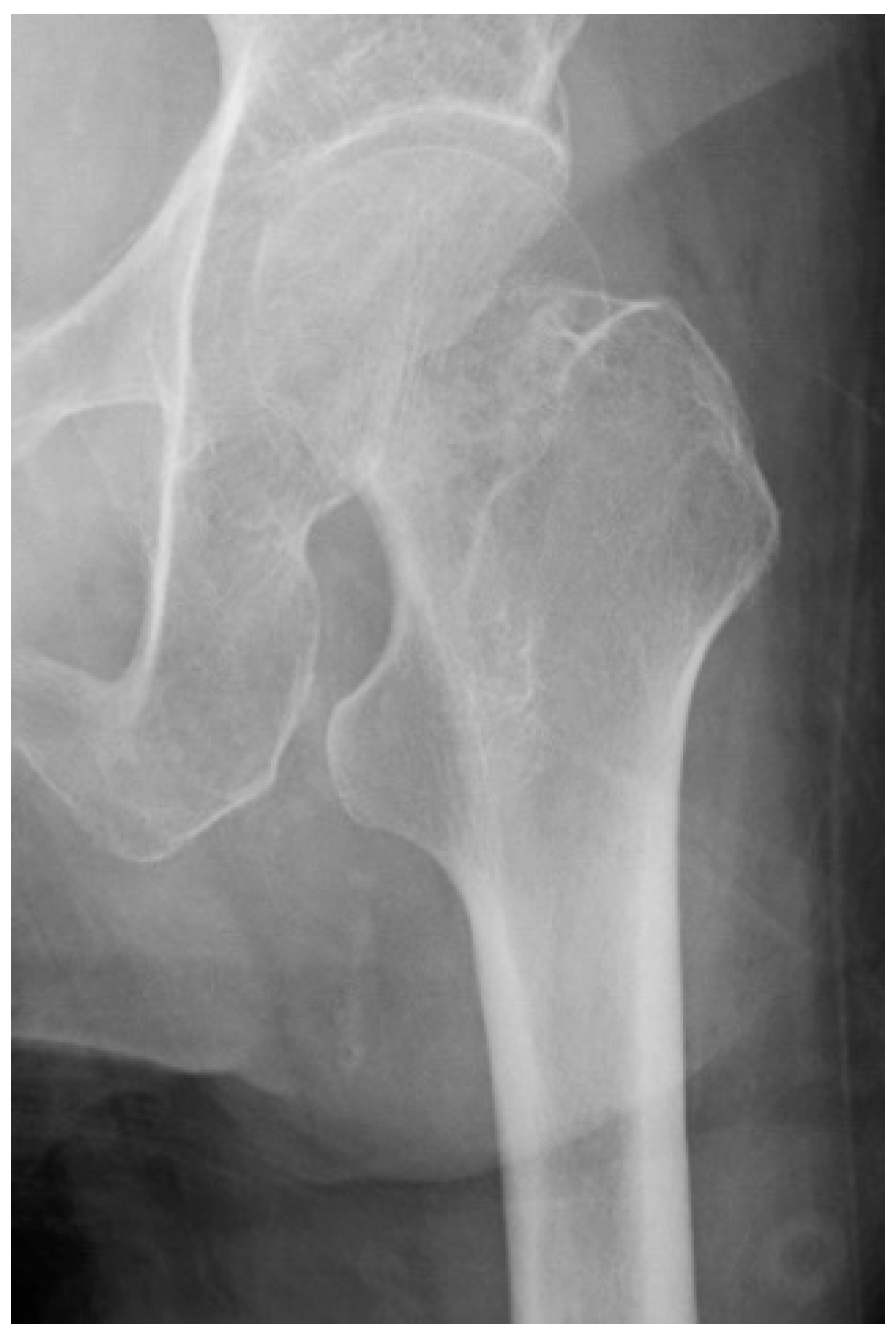

2.3. AP Hip Radiographs

2.4. Radiographic Measurements

2.5. Garden Alignment Index

2.6. Valgus Tilt Measurement